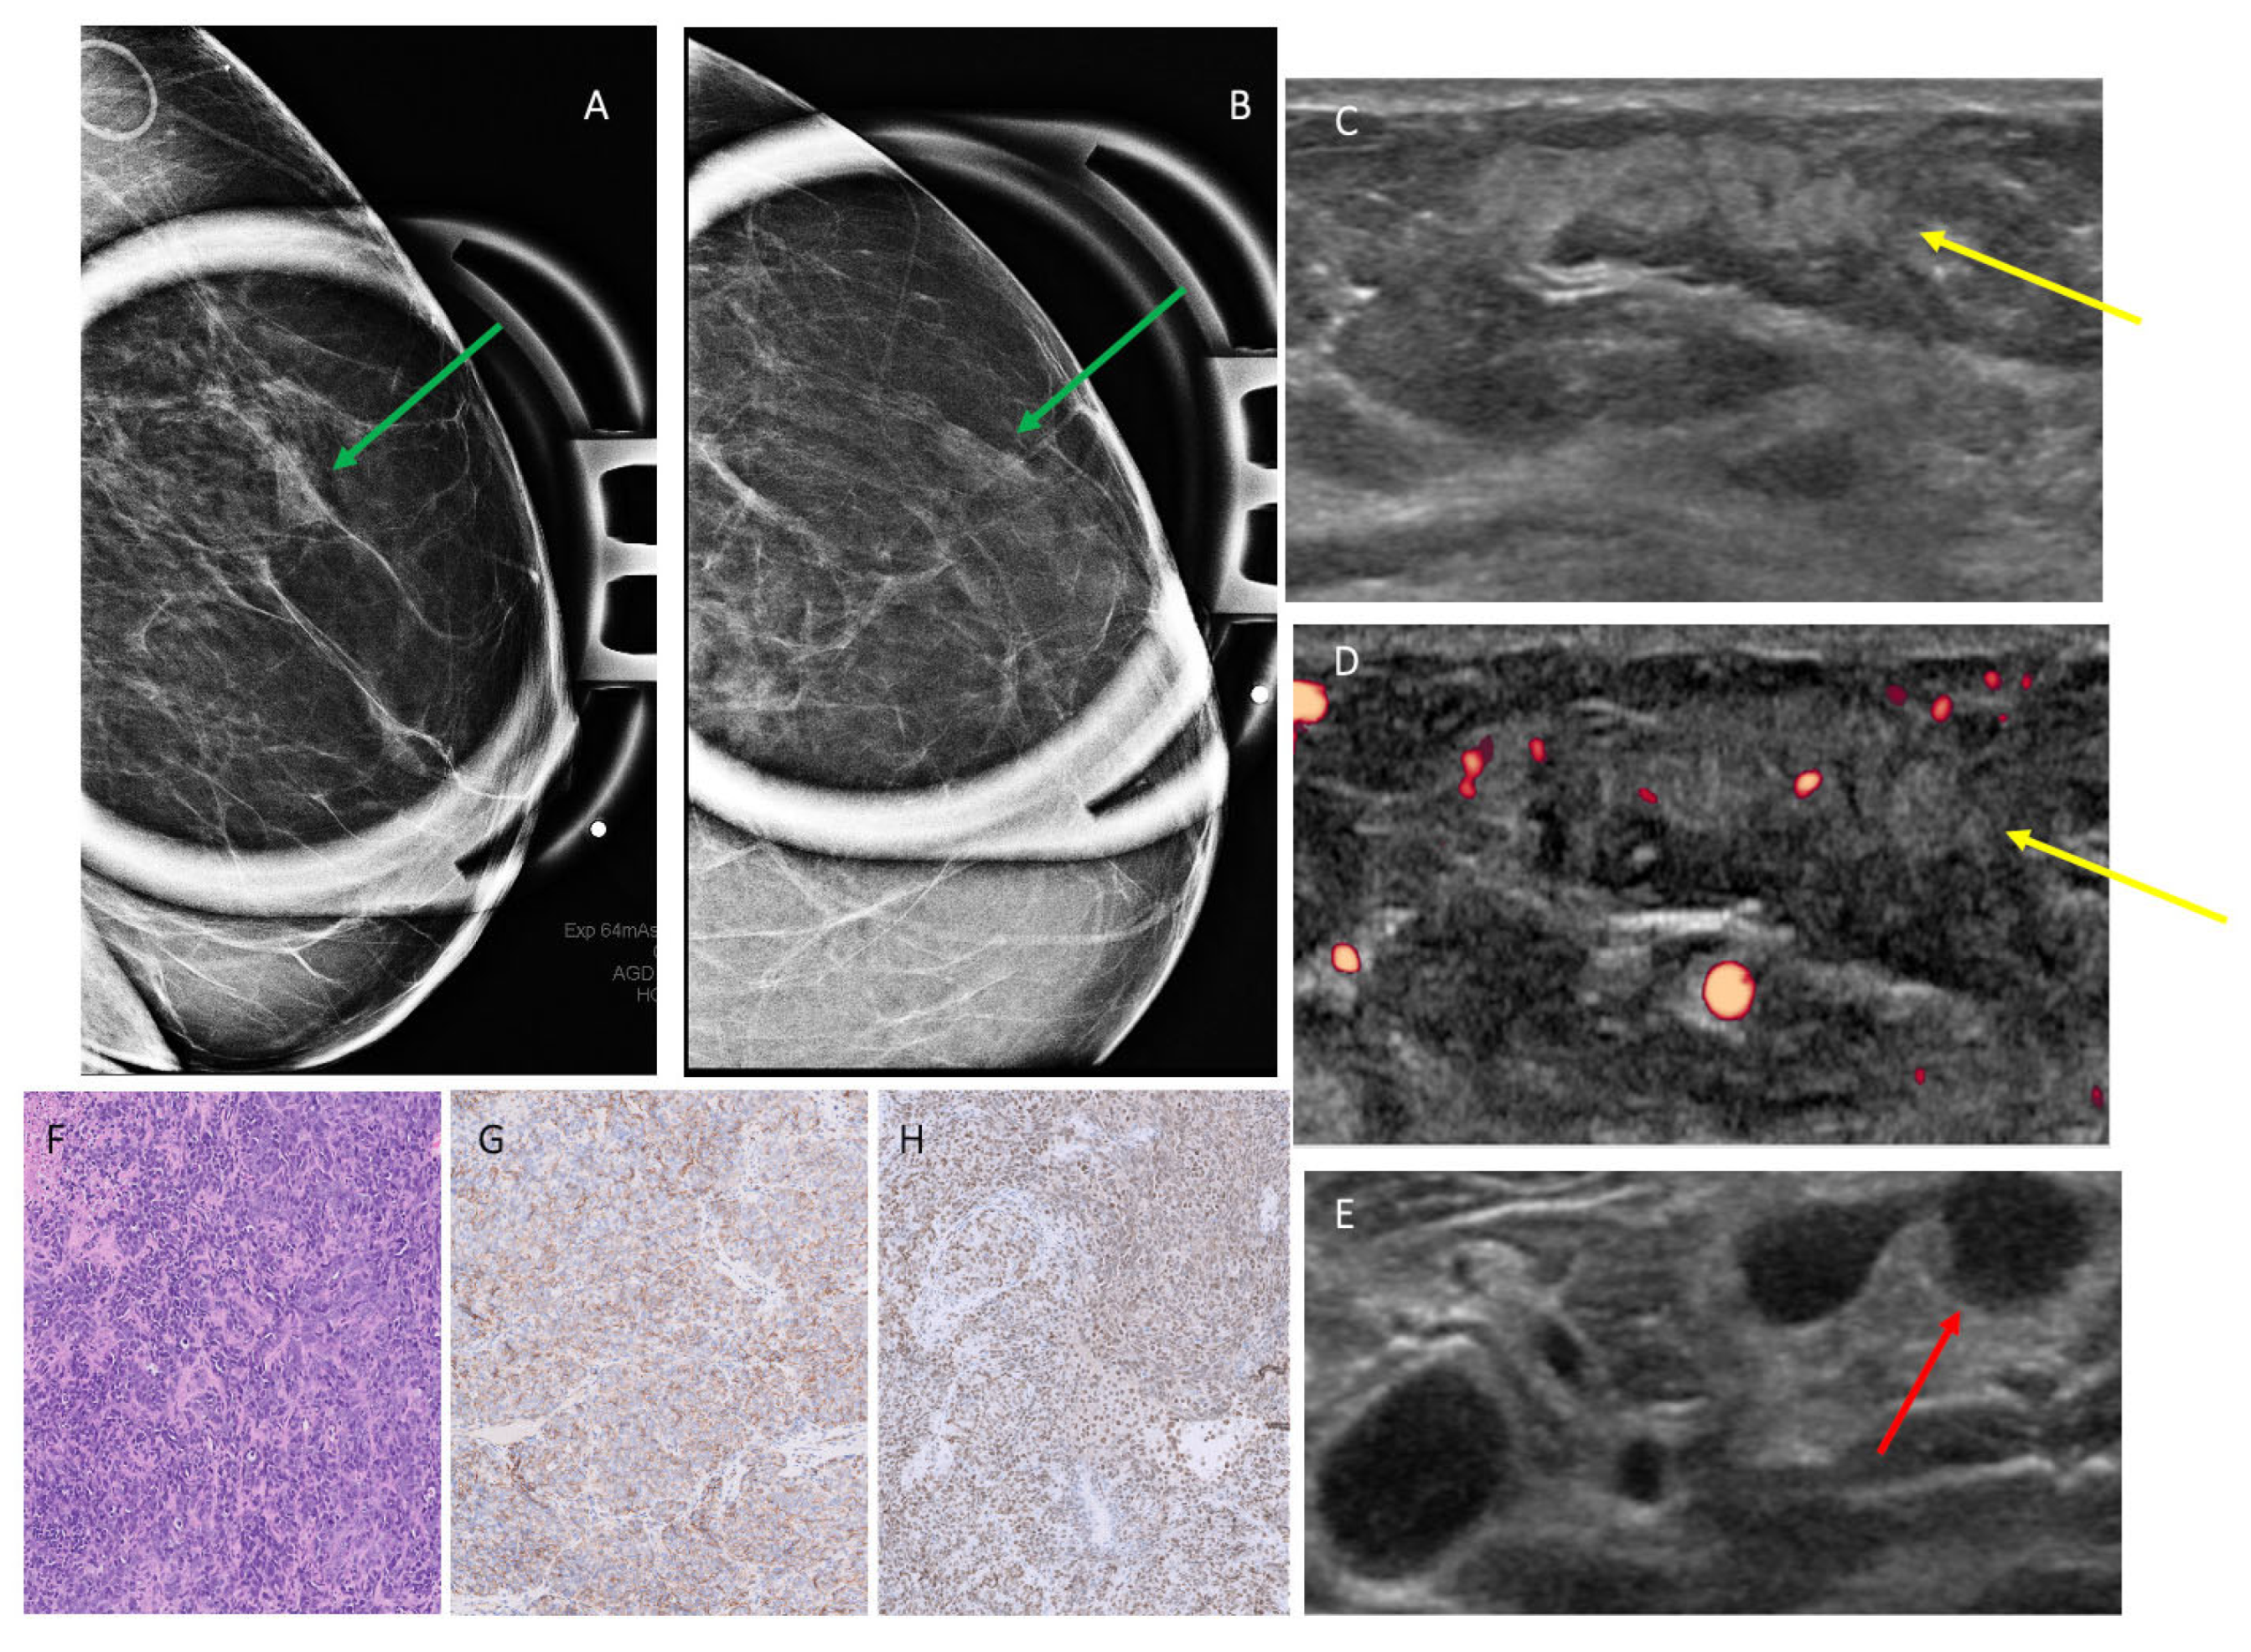

| 1 | 1.8 | Ultrasound core needle biopsy | Irregular high-density mass with indistinct margins | Irregular, non-parallel hypoechoic mass with microlobulated margins, posterior acoustic enhancement and no Doppler flow | Suspicious, 4A–4B | Irregular mass with irregular margins and heterogeneous enhancement |

| 2 | 1.4 | Ultrasound core needle biopsy | Global asymmetry | Irregular, non-parallel, heterogeneous mass with indistinct margins, posterior acoustic shadowing and Doppler flow | Suspicious, 4A–4B | N/a |

| 4 | 3.5 | Ultrasound core needle biopsy | Focal asymmetry associated with amorphous calcifications | Irregular, parallel, hypoechoic mass with indistinct margins, posterior acoustic shadowing and Doppler flow | Probably Malignant, 4C | N/a |

| 10 | 2.5 | Ultrasound core needle biopsy | Irregular high-density mass with indistinct margins | Irregular, parallel, heterogeneous mass with indistinct margins, posterior acoustic enhancement and Doppler flow | Suspicious, 4A–4B | Irregular mass with irregular margins and heterogeneous enhancement |